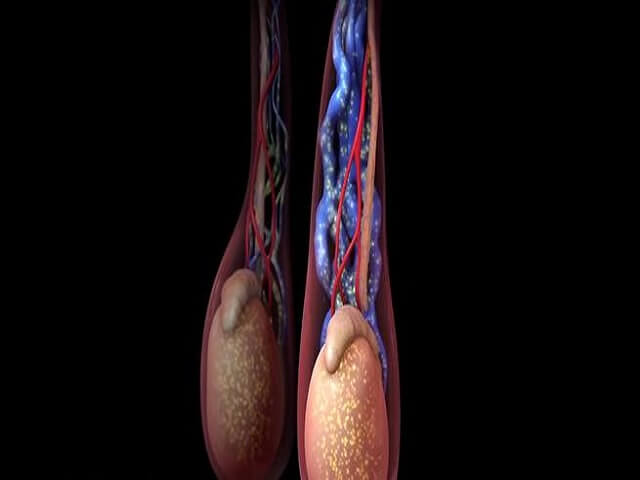

有没有男性精索静脉曲张的图片?不同程度有什么区别?

在临床上把精索静脉曲张分为三个程度,轻度精索静脉曲张,在超声测得精索静脉的直径在2.2-2.7mm之间,中度精索静脉曲张,在超声下测得的精索静脉直径达到了2.8-3.1mm之间,重度精索静脉曲张,在超声下测得的精索静脉直径达到了3.1mm以上。一般轻度的精索静脉曲张是没有什么特别的症状的,也是不需要进行特别的治疗的,但是中度和重度的精索静脉曲张就需要引起重视了,可能会导致睾丸萎缩,造成少精、弱精、...